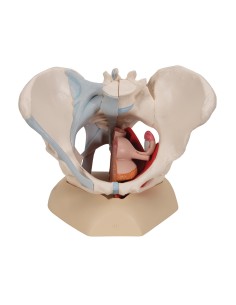

3B Modèle scientifique et gynécologique pour l'entretien avec les patientes P53

3B Scientific. Kit d'enseignement, système de reproduction femelle W40214

3B Modèle anatomique scientifique du bassin gravide, décomposable en 3 parties L20

Pelvis masculin 3B Scientifique avec ligaments, vaisseaux, nerfs, plancher pelvien et...

Modèle anatomique du squelette du bassin d'un homme 3B Scientific H21/1

3B Bassin scientifique, anatomique Modèle pour illustrer l'accouchement L30

Des modèles anatomiques détaillés pour tous les besoins

Du crâne en 22 parties à verrouillage magnétique aux modèles de colonne vertébrale, des modèles d'articulation aux modèles de cœur, chaque pièce de notre collection est conçue pour une immersion totale dans l'étude de l'anatomie humaine. Nos modèles, réalisés à partir de scans d'os réels, garantissent une expérience tactile authentique et une fidélité de poids presque identique aux originaux.

Indispensables aux étudiants comme aux professionnels, nos modèles anatomiques sont des outils pédagogiques qui permettent d'observer les structures anatomiques avec précision, en évitant les dissections ou les études invasives. Ils sont également utiles pour expliquer les pathologies aux patients, ce qui rend la communication plus efficace et permet de gagner un temps précieux.